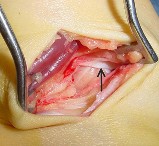

Question 10:

A 45-year-old male sustains a high-energy Schatzker IV tibial plateau fracture. Given the classic displacement pattern of this specific injury, which of the following is the most appropriate surgical approach and fixation strategy to properly neutralize the deforming forces?

Correct Answer: Posteromedial approach with a medial buttress (anti-glide) plate

Explanation:

A Schatzker IV fracture involves the medial tibial plateau and is typically the result of high-energy varus forces, often combined with an axial load. The primary deforming force drives the medial fragment into varus and posterior subluxation. The biomechanically sound treatment requires a posteromedial approach with a medial buttress (or anti-glide) plate to physically resist the varus and posterior displacement.